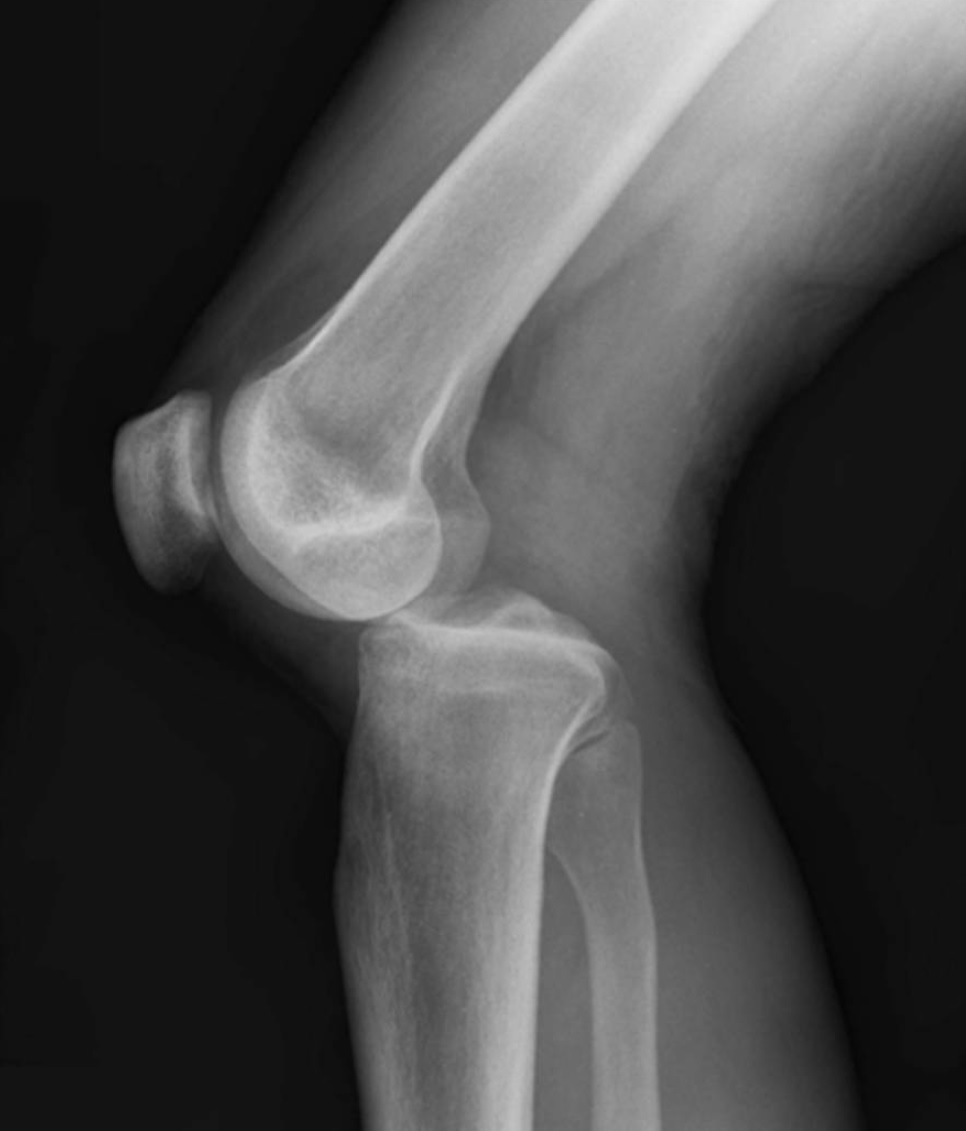

Anteroposterior knee dislocation

Loss of normal contour

Extended